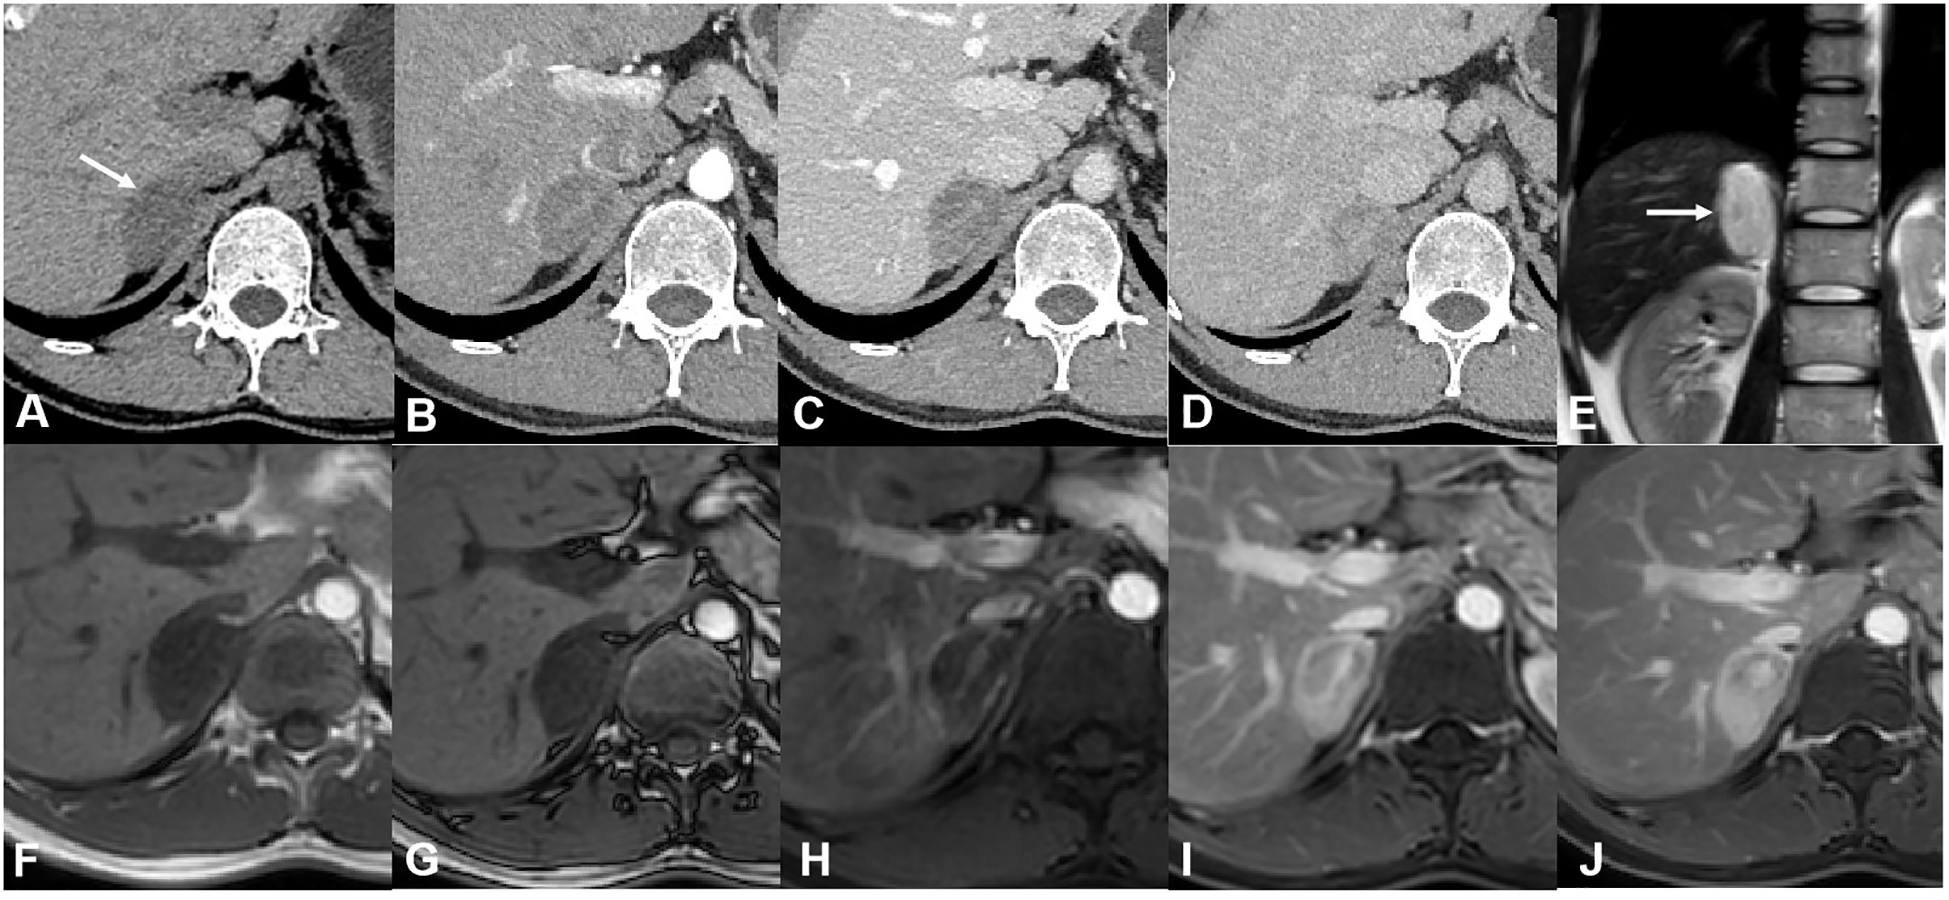

For case 2, CT revealed a mixed-density lesion with well-defined margins in the right adrenal region, approximately 3.5 cm × 2.5 cm in size. The mass exhibited moderate enhancement with delayed washout, showing a mean attenuation value of 34 HU on plain CT and 71 HU on the delayed phase (in the range of moderate enhancement). On MR imaging, the lesion appeared as a mainly solid mass, hypointense on T1-weighted images and hyperintense on T2-weighted images. After contrast injection, the lesion was progressively impregnated by the contrast agent from the periphery to the center and presented delayed washout. Some interior areas of the tumor ultimately showed relatively poor enhancement (Figure 2). Based on these findings, a ganglioneuroma was presumed.

CT and MR images of case 2. (A) Axial plain CT images showed a well-defined mass with a mean attenuation value of 34 HU on the right adrenal region. Axial enhanced CT of arterial (B), venous (C), and delayed (D) phases showed moderate enhancement and delayed washout of the tumor (the mean attenuation value was 71 on the delayed phase). (E) Coronal T2-weighted image showed hyperintensity of the tumor. No signal change was shown between in-phase (F) and out-of-phase (G) axial T1-weighted images. (H) Enhanced MR images of the arterial phase showed a small vessel crossing the tumor. Venous (I) and delayed (J) phases of enhanced MR images showed the contrast agent progressively impregnating the tumor from the periphery to the center. There was a relatively poor enhancement area in the interior of the tumor.